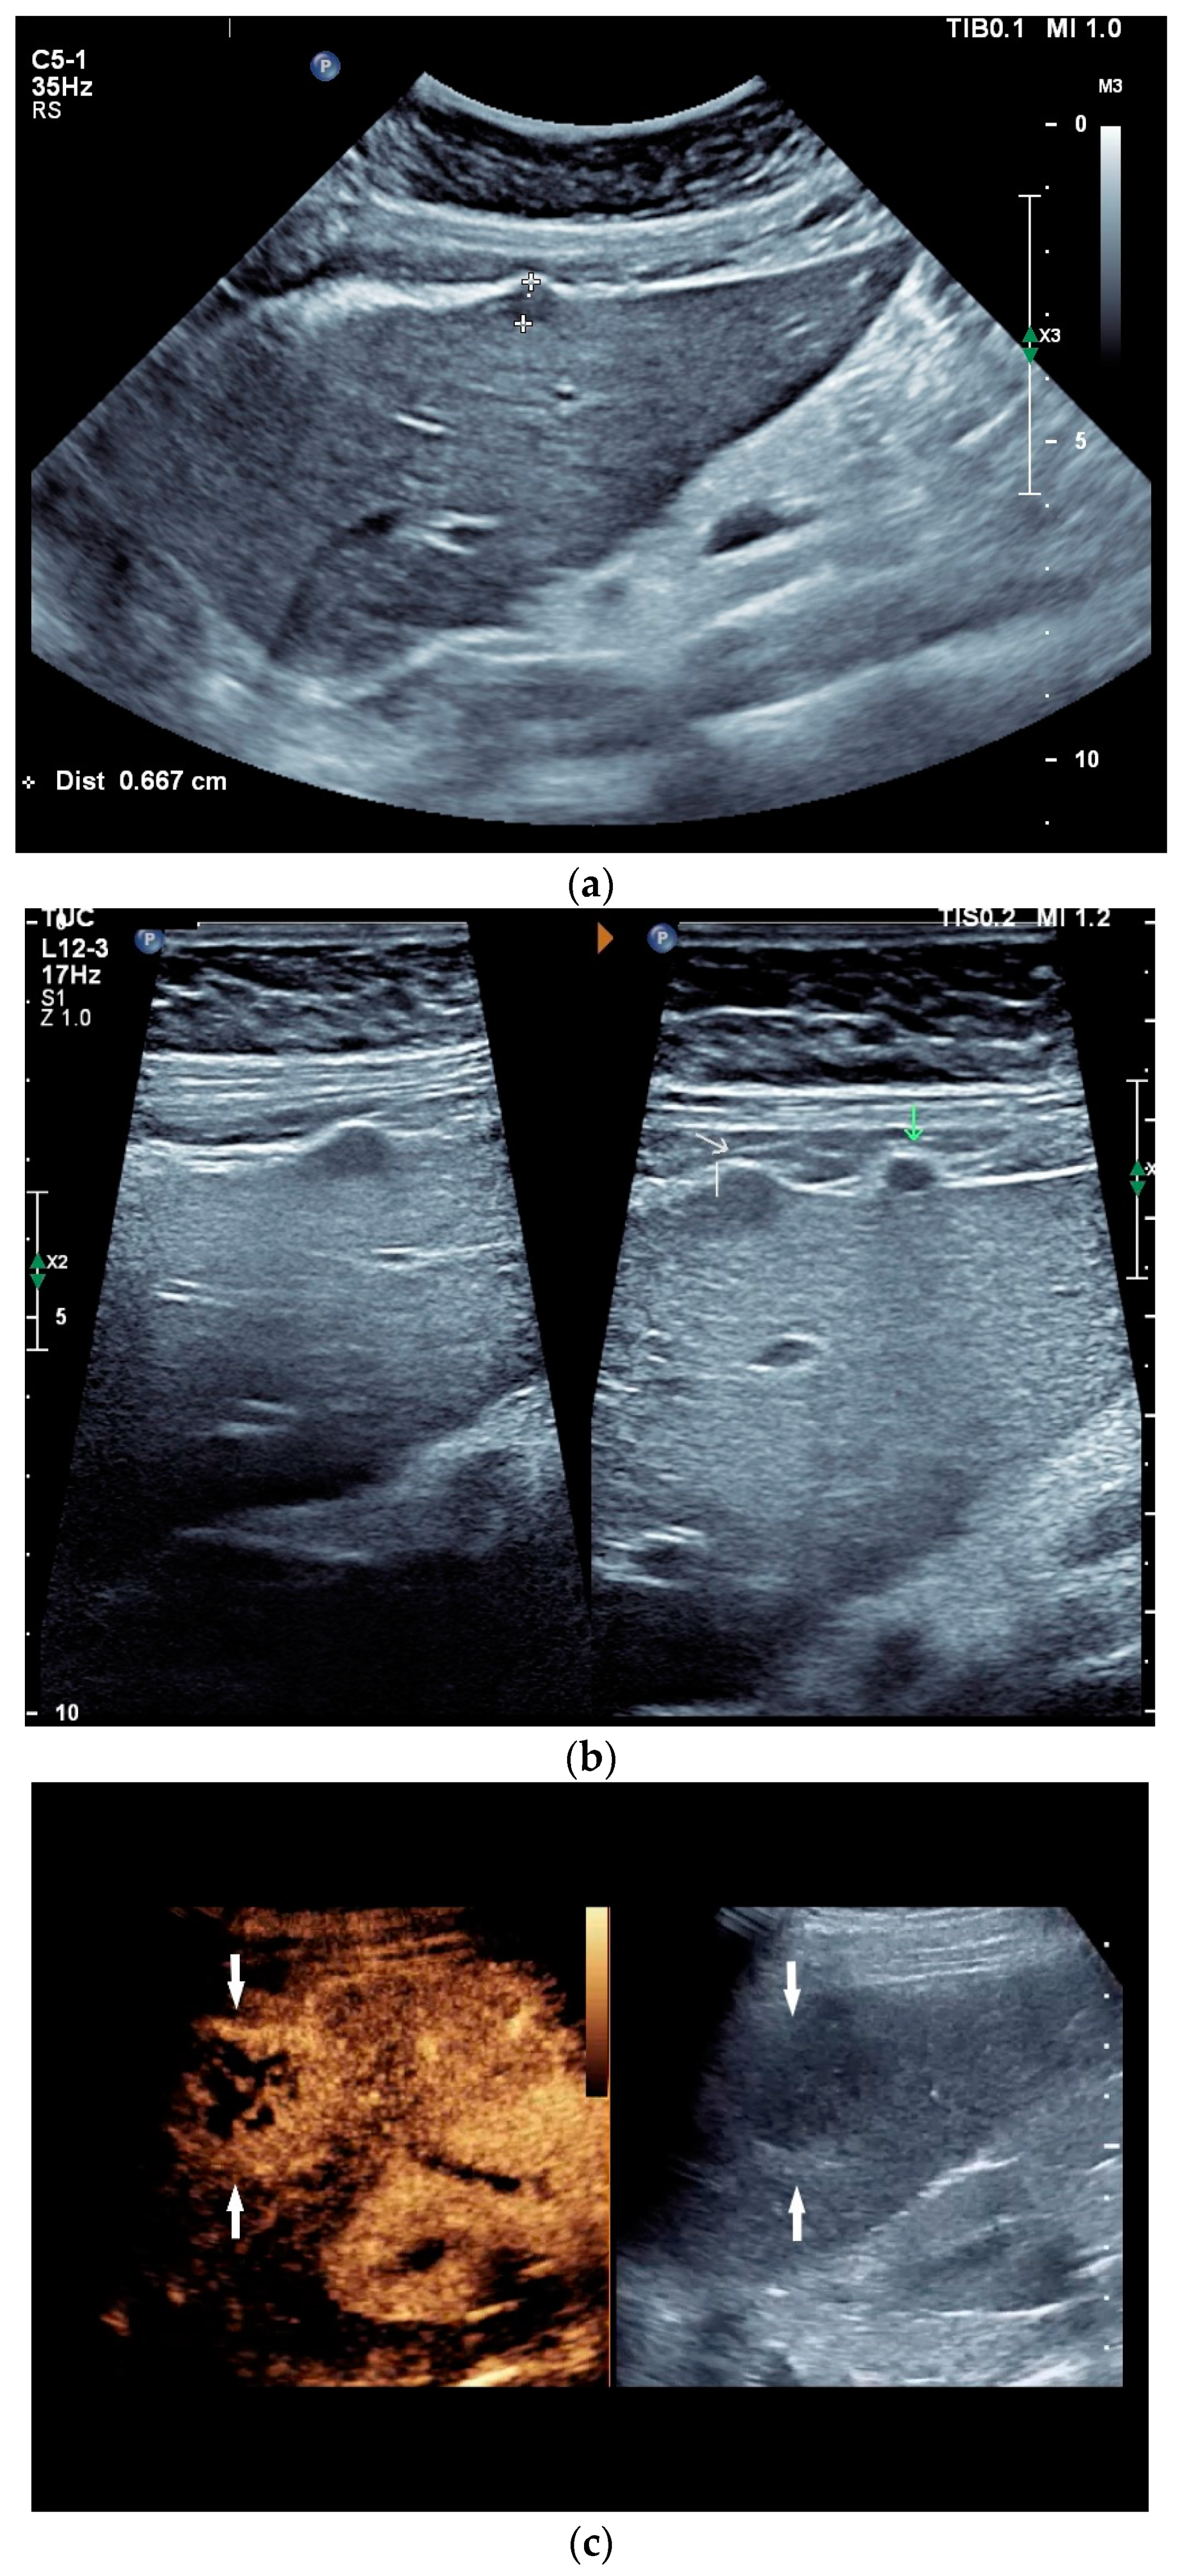

What can be seen sonographically? Ascites can be either diffuse or focal type [Figure 1a,b]. Due to the protein and cell content, these tend to be echogenic, rather than non-echoic. Attention must be paid to enlarged lymph nodes at the same time. Any thickening of the peritoneum and mesentery must be specifically searched for. This also applies to macronodular changes in the peritoneum and mesentery [Figure 1c–h]. The smallest speck-like deposits are usually not visible on ultrasound [36]. With ascites, it may be possible to observe the adhesions [31,37]. Kumar et al. were able to histologically detect granulomatous inflammation in 17/19 (89%) patients using ultrasound-guided needle biopsy of omental thickenings. In a country like India, the authors interpreted this as a manifestation of tuberculosis [32].

Figure 1.

Typical changes in the peritoneum, mesentery, and omentum in patients with tuberculosis. Ascites with pronounced septa (a). Ascites encapsulated between the abdominal wall and colon (b). Omental thickening with non-echoic caseous abscesses and few echogenic contents (c); hypoechoic nodules in hyperechoic thickened peritoneum (d). Significantly thickened hyperechoic peritoneum in B-mode US (right side of image) (marked with arrows). In CEUS, the thickened peritoneum is contrast enhanced in the arterial phase (e). In the parenchymal phase, it shows a decrease in enhancement (f). The thickened hyperechoic peritoneum shows a non-echoic lesion (arrow) (g). In the CEUS, this is not enhanced and instead shows a hyperenhanced rim. This corresponds to caseous necrosis (h).